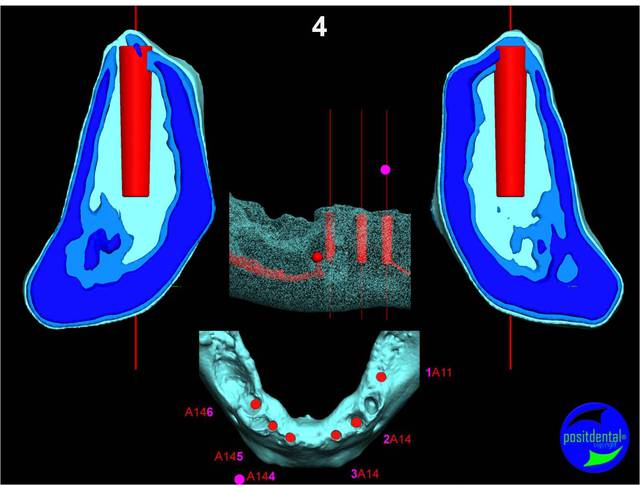

Extraction, pose d’implants Ankylos, pose des piliers Standard définitifs, mise en charge immédiate bi-maxillaire en une chirurgie.

Maxillaire supérieur – extraction 13, 26, 7 implants en MCI, 1 implant en MCR pose summeurs, densification par ostéotme, comblement osseux, bridge provisoire sans fausse gencive avec renfort métallique.

Maxillaire inferieur – extraction 35, 34, 44, 45, 6 implants MCI, comblement osseux, bridge provisoire sans fausse gencive avec renfort métallique.

en attendant la pano voici les coupes de la S.I.A.O.